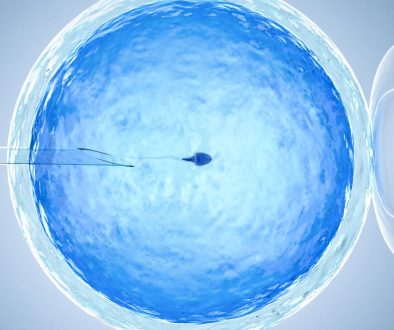

التبويض هو عملية شهرية تحدث عند المرأة، حيث يطلق المبيض بويضة ناضجة يمكن أن تُخصب بواسطة الحيوان المنوي. يحدث التبويض عادة في منتصف الدورة الشهرية، تقريباً في اليوم 14 من دورة تستمر 28 يوماً.